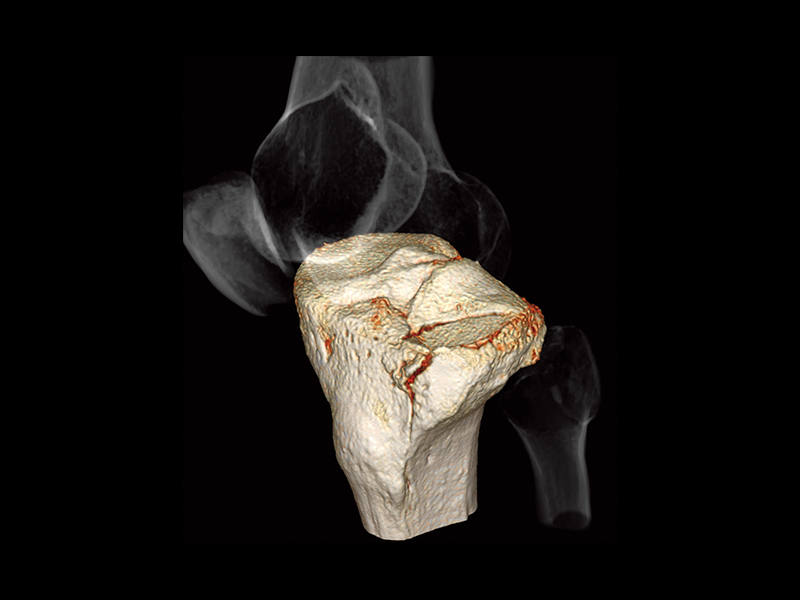

Tibial plateau fracture

- * Images other than the axial image were processed by the 3D image analysis system SYNAPSE 3D.